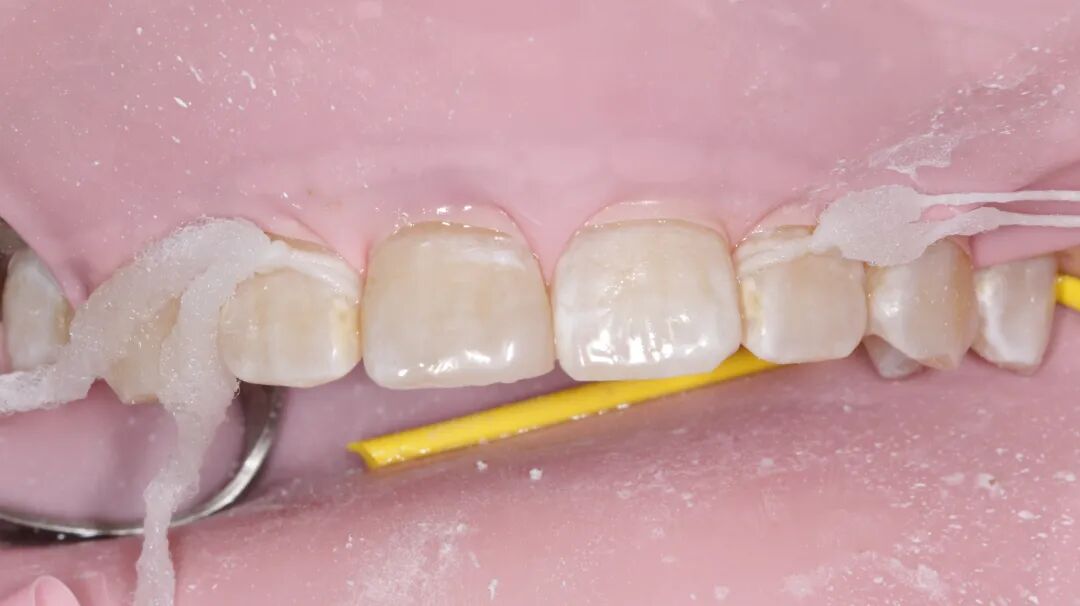

上颌中切牙瓷贴面美学修复

性别:女     年龄21岁

主诉:前牙氟斑牙影响美观

现病史:病人因从小有高氟地区生活史,导致全口氟斑牙,现因前牙区氟斑牙呈黄褐色影响美观,要求处理

检查:牙龈无红肿,口内卫生良好

治疗方案:铸瓷贴面美学修复